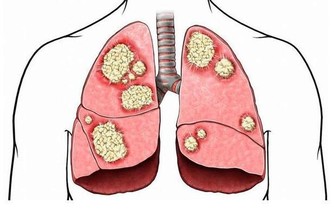

4、需排除腫瘤可能——待著不動也疼

出現不明原因的腰疼,又找不到特殊的壓痛點,夜間睡著時也疼得厲害,

處於舒適、放鬆的休息狀態時仍然很疼,必須及時到醫院排除是否為腫瘤,以免延誤治療。